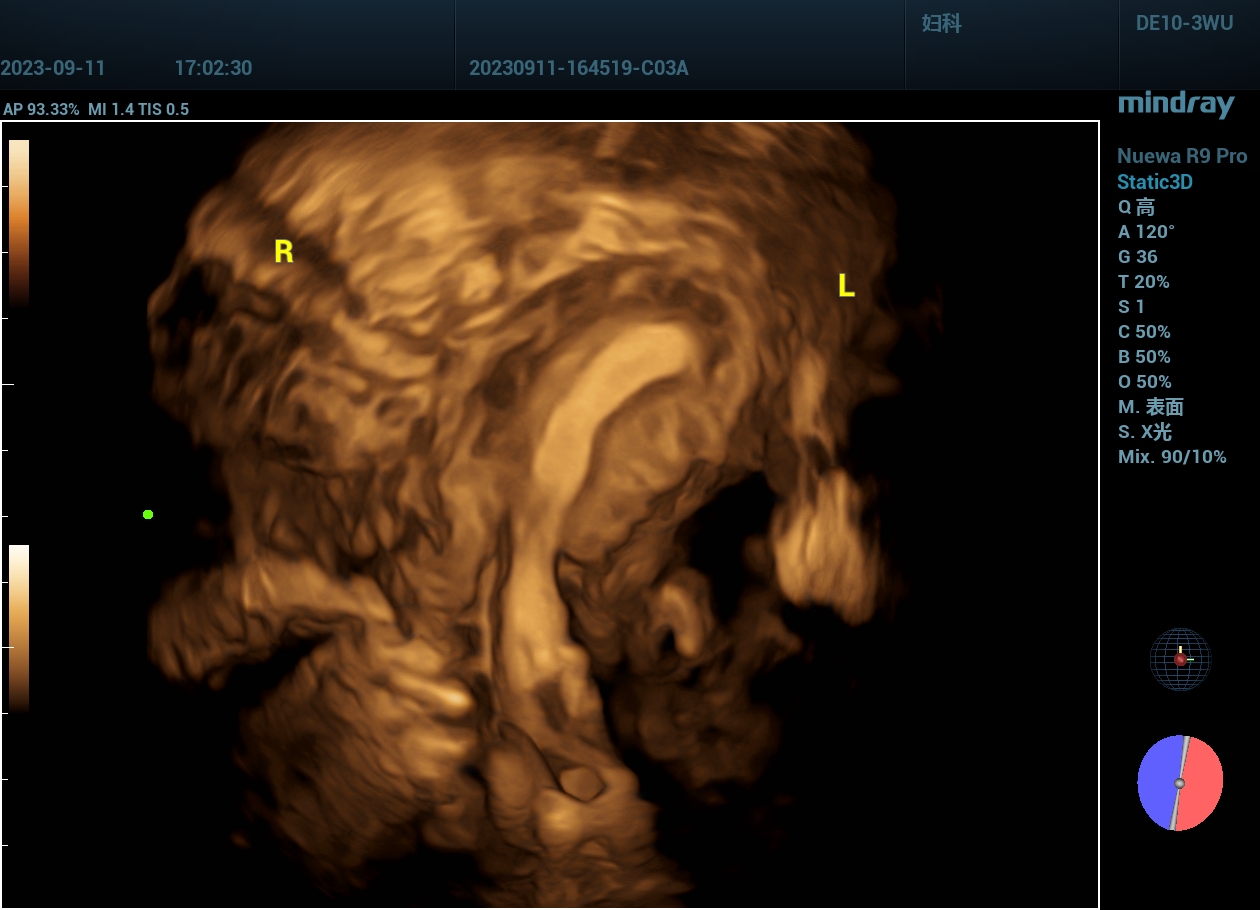

病例,单角子宫:宫腔形态异常,二维+三维

www.jinrichaosheng.com